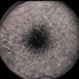

- XLinked Retinoschisis Female

- Condition/keywords

- x-linked retinoschisis (XLRS)

- 34-year-old white female, x-linked retinoschisis.